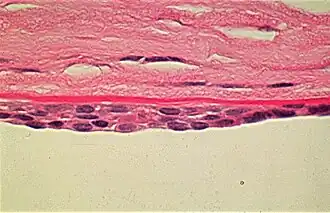

Эндотелий роговицы, задний эпителий роговицы — монослой специализированных плоских клеток, выстилающих заднюю поверхность роговицы и входящих в соприкосновение с содержимым передней камеры глаза. Гексагональные клетки эндотелия содержат повышенное количество митохондрий и осуществляют транспорт жидкости и растворенных веществ, поддерживая роговицу в слабо дегидрированном состоянии, необходимом для её прозрачности. Площадь клеток примерно одинакова; при значительном разбросе их размера говорят о наличии полимегетизма.